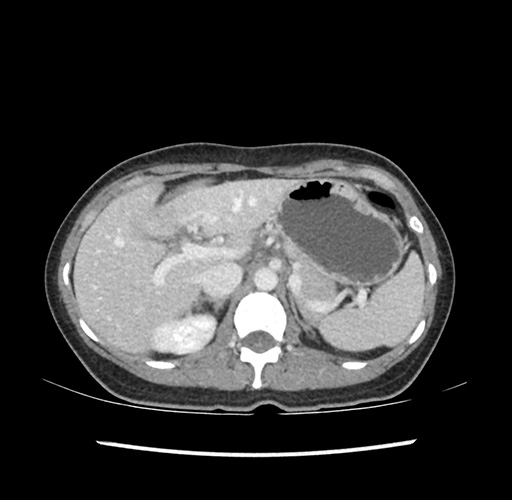

Imaging Analysis

Look through the patient's CT scan to identify any areas of concern for the necessary procedure.

Based on your CT findings, which issue(s) would give reason for "planned slowing down moment(s)" in this case?

Considering a standard left lateral sectionectomy procedure, what step(s) of the operation would you do differently in this case ?